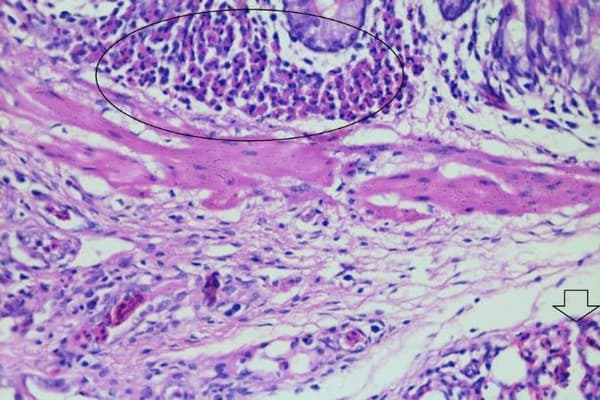

In Bone marrow, the histopathological changes in bone marrow varying from myeloid cells proliferation to enlarged haemopoietic sinusoids filled with erythroblasts and myeloid cells.

Role of histopathological examination in diagnosis of avian leucosis virus subtype J in broiler chicken in Egypt - Image 35

Fig (38) bone marrow of AR breeds 4weeks broiler chickens x400 H&E showing myeloid cells proliferation (circle).

Role of histopathological examination in diagnosis of avian leucosis virus subtype J in broiler chicken in Egypt - Image 36

Fig (39) bone marrow of HD 3weeks broiler chickens x400 H&E showing myeloid cells.